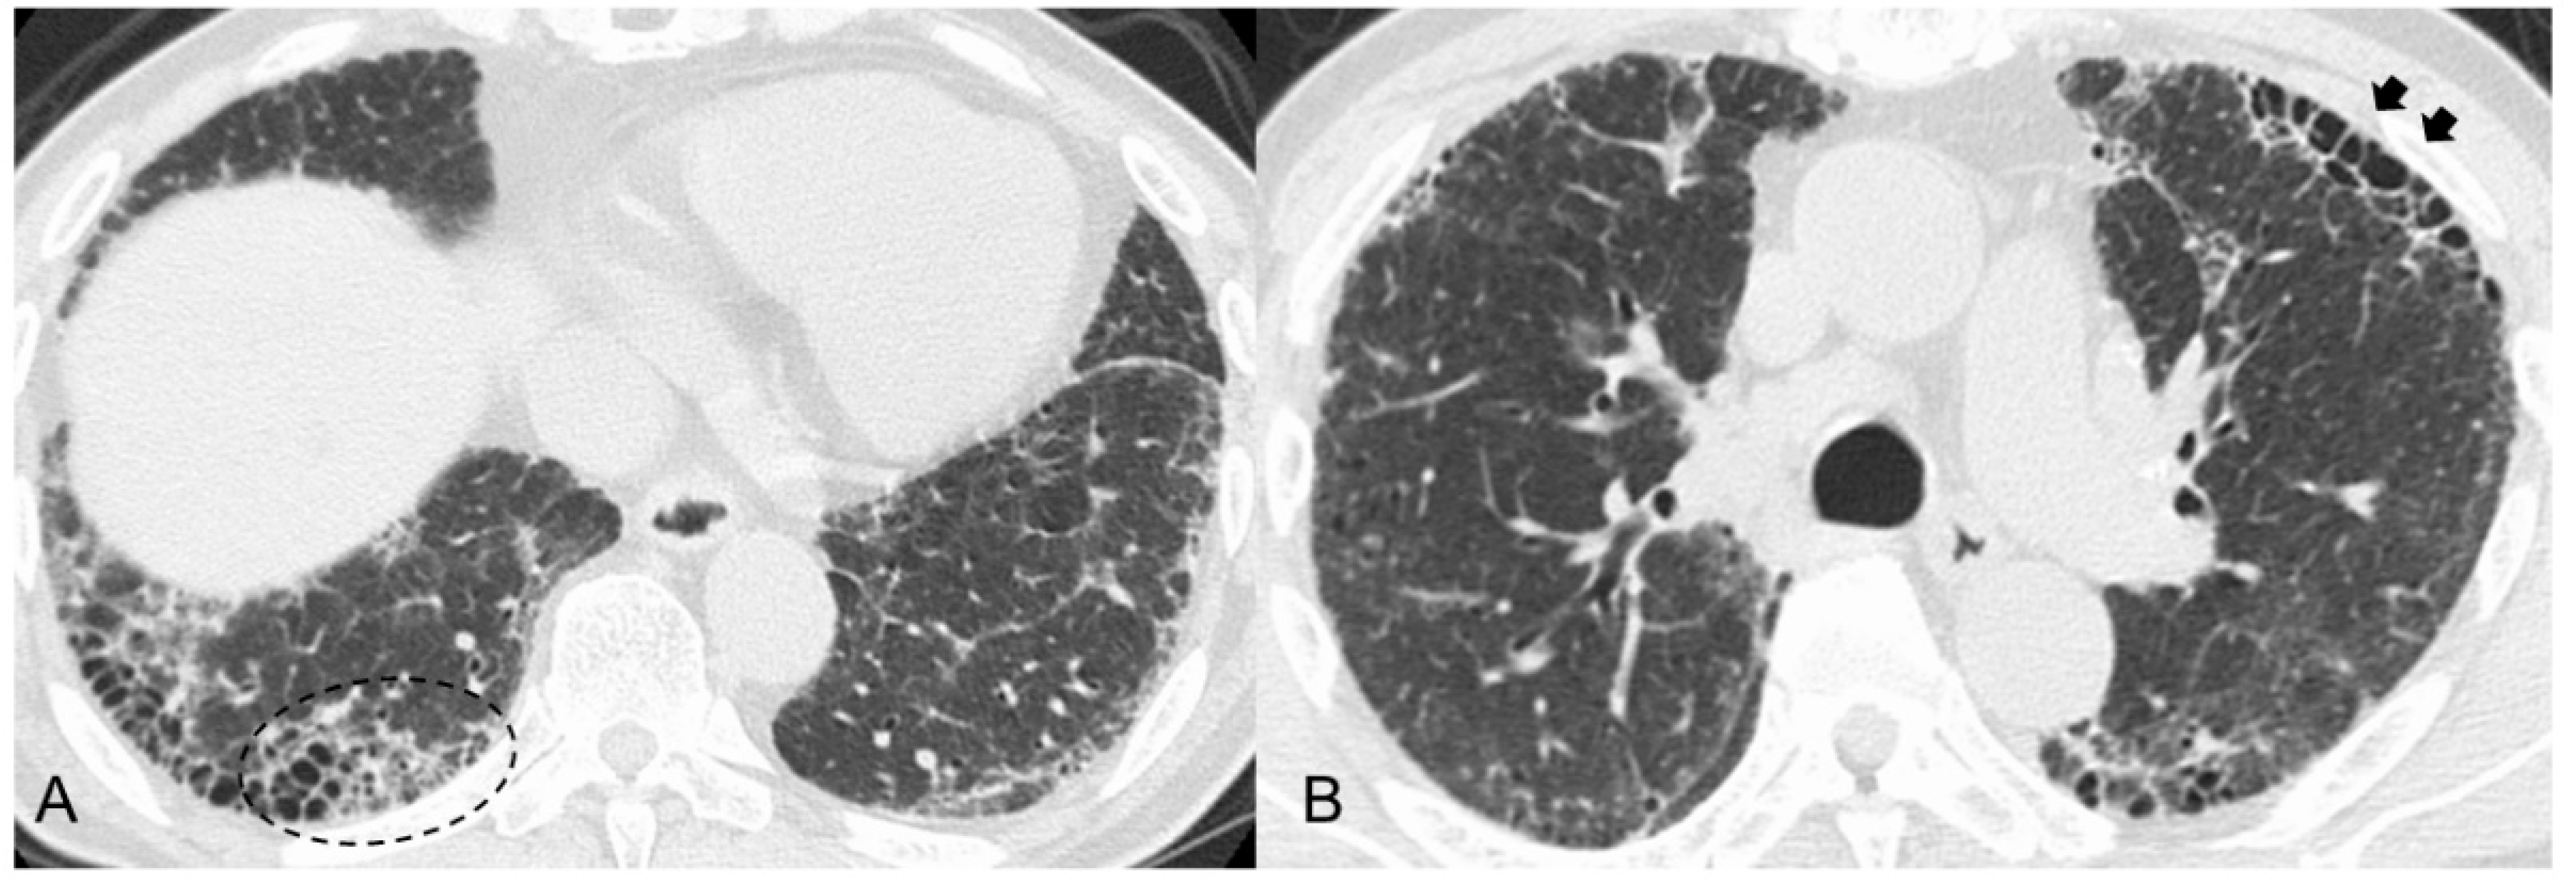

| HRCT findings | Framework: Subpleural and basal predominant distribution is often heterogeneous | |

| Increased attenuation around honeycombing and traction bronchiectasis (19–39%) | ― | |